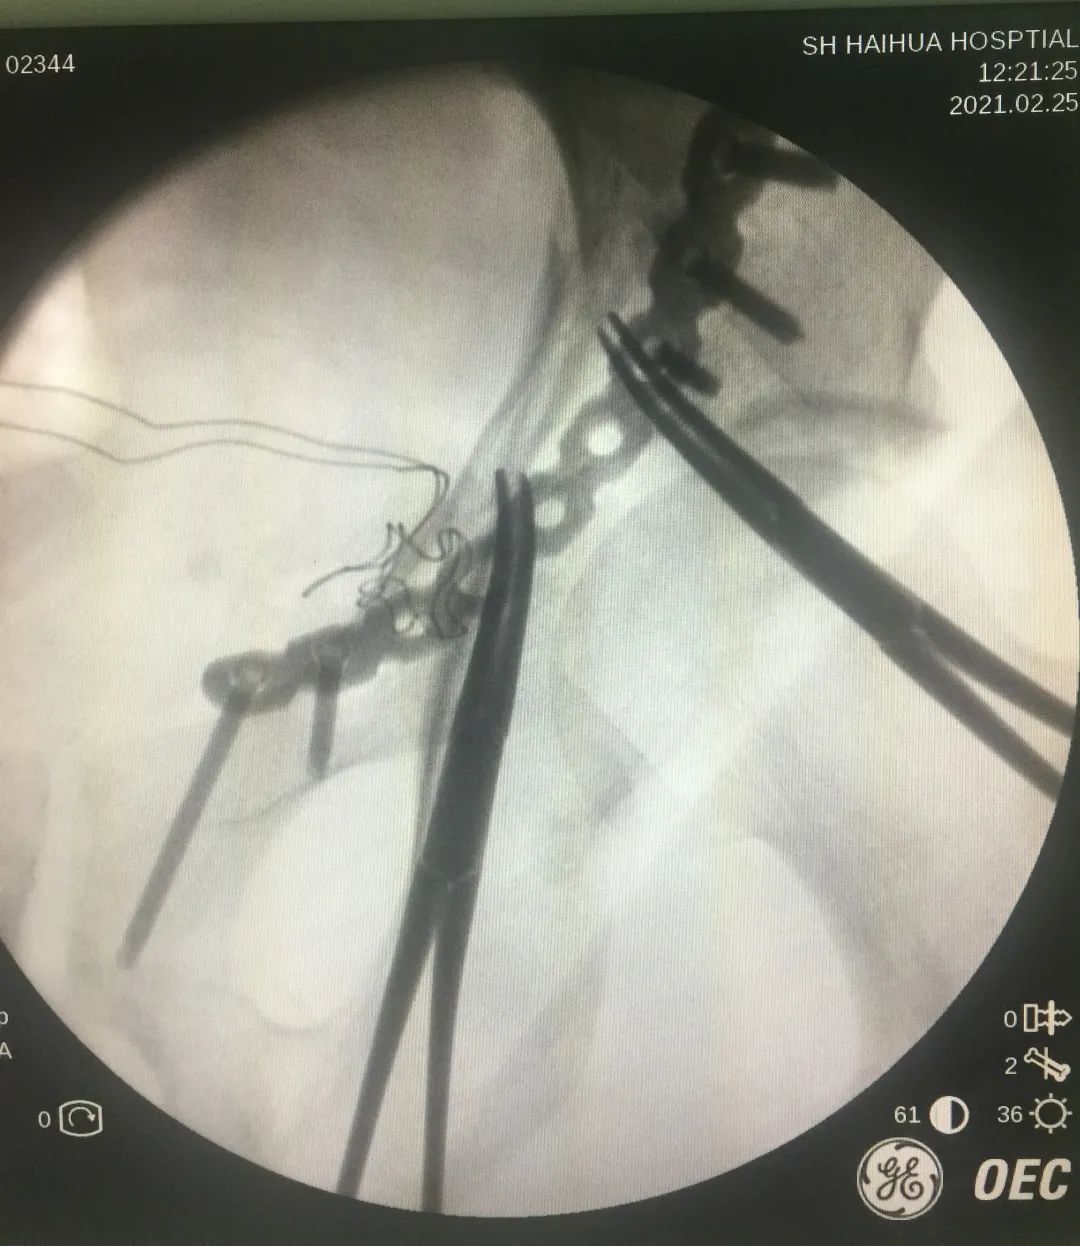

他在工地上不慎从高处坠落。当时他左侧肢体着地,左髋关节剧烈疼痛,不能站立行走,被紧急送来上海海华医院急诊,诊断其为「左侧髋臼粉碎性骨折,左侧坐骨支骨折」,科室立即准备急诊手术。

患者骨盆影像学资料

因此,经过又一轮缜密的术前讨论,科室决定抛弃传统方式,为患者行腹直肌旁入路微创手术这种新的切口方式。极大地减少出血量,降低手术风险。

腹直肌旁入路微创手术

万幸的是,最终在骨科、外科、麻醉科及手术室护理团队多学科的严密配合和高超技术下,克服了多种难题,成功为患者实施了一台高质量的手术,术中出血量约 50 ml,非常顺利。患者目前病情稳定,复位良好,复查各项指标良好,确定不需要输血,等一切稳定之后即可出院。